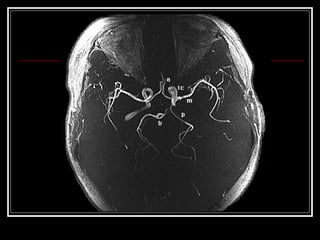

Exames de Imagem Qual a primeira escolha na emergência? Por quê? Qual o método mais sensível?

Exames de ImagemQual a primeira escolha na emergência? Por quê? Qual o método mais sensível?